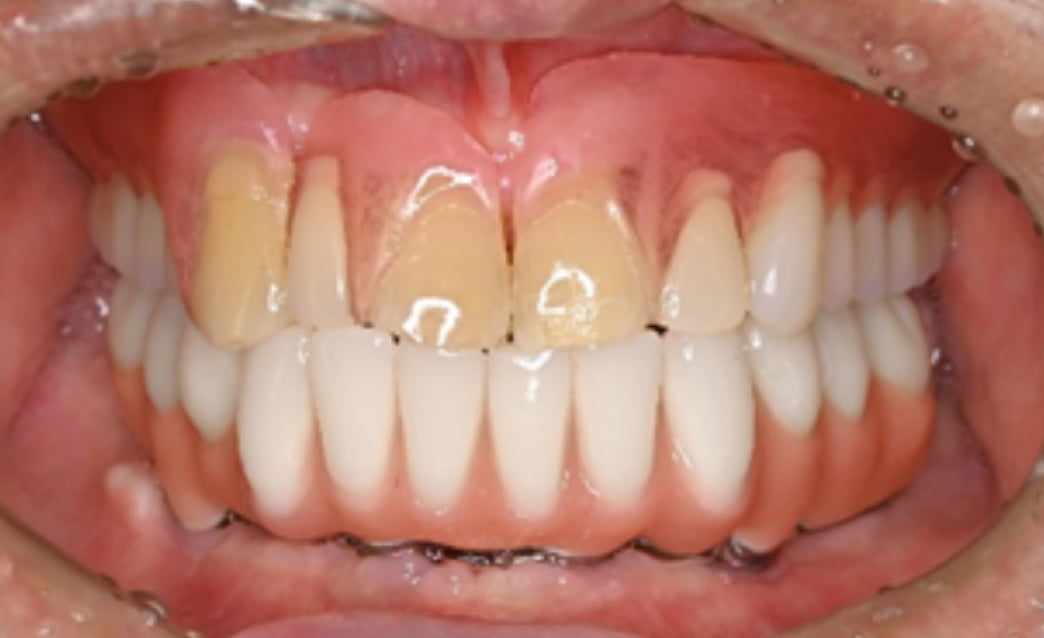

60代

Before

After

| 主訴 | 入れ歯が合わない。 |

| 治療内容 | 下顎の残存歯は、歯周病が進行していたため全て抜歯をおこない、同日にインプラント埋入と仮歯の装着をしました。骨とインプラントが固定されるのを約3ヵ月待ち、型どりをして最終補綴を装着します。上顎にはノンクラスプデンチャーを使用し、快適に食事がとれています。 |

| 治療期間 | 6ヵ月 |

| 費用 | ¥3,586,000(税込み) |

| リスク・副作用 |

外科処置が必要。コストがかかる。 |